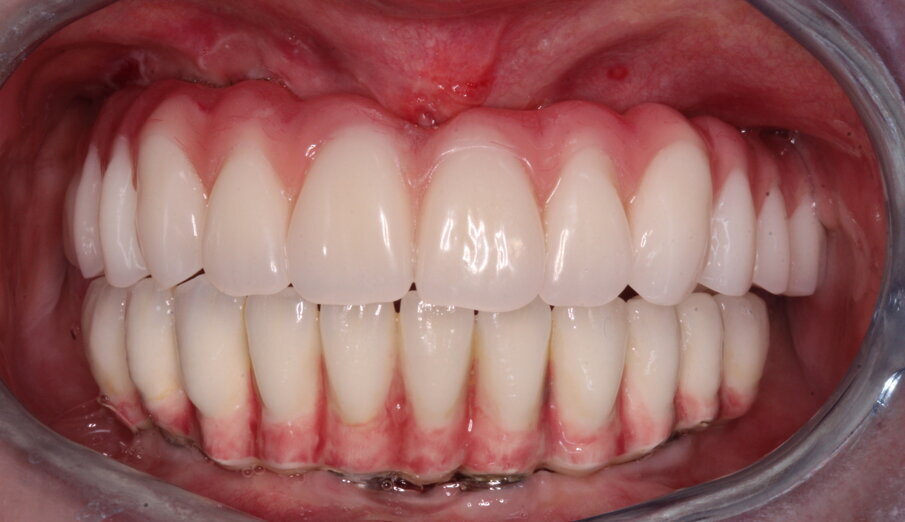

Il giorno dopo il tecnico confeziona una protesi definitiva tipo Toronto Bridge con rinforzo in Peek o altro tecnopolimero di resina termoindurente rinforzata (Trilor Arch) immerso all’interno della resina, rispettando l’aspetto estetico definito in precedenza e l’altezza verticale. Nella sua parte inferiore, la protesi presenta delle concavità in corrispondenza degli impianti e dei monconi che appaiono leggermente più grandi del diametro e dell’altezza delle cappette. Una volta verificato in bocca che la protesi sia passiva e che le cappette non frizionino alcuna parete dei fori, si termina il lavoro colmando con della resina composita Combo-Lign (bredent) lo spazio tra la cappetta e la protesi scavata precedentemente dal tecnico facendo articolare l’arcata in corso di trattamento con l’antagonista mediante una chiave articolare in silicone rigido.

La resina alla stato ancora tenero va indurita con la lampada polimerizzante per alcuni minuti; una volta controllata la masticazione anche senza la chiave articolare e fatti gli opportuni minimi ritocchi, la protesi va rimossa e rifinita a dovere, poi riaccoppiata. Una OPT di conferma serve per verificare il corretto alloggiamento delle cappette sui monconi e la passività del manufatto.

Per il paziente non ci sono fori antiestetici, in tempi rapidissimi si ottiene il definitivo (in mezza giornata) senza passare attraverso il provvisorio, si sfrutta il carico immediato anche in condizione post-estrattiva; durante le sedute di igiene orale la rimozione è facilitata ogni qualvolta lo si desideri e la seduta alla poltrona è rapidissima. Altri vantaggi prevedono l’utilizzo di poche componenti protesiche, abbassa quindi notevolmente i costi di esecuzione, con il vantaggio che il reintervento per fallimento implantare si può eseguire senza compromettere la protesi, come pure l’aggiunta di un impianto e collegarlo alla protesi può essere fatto senza problemi.